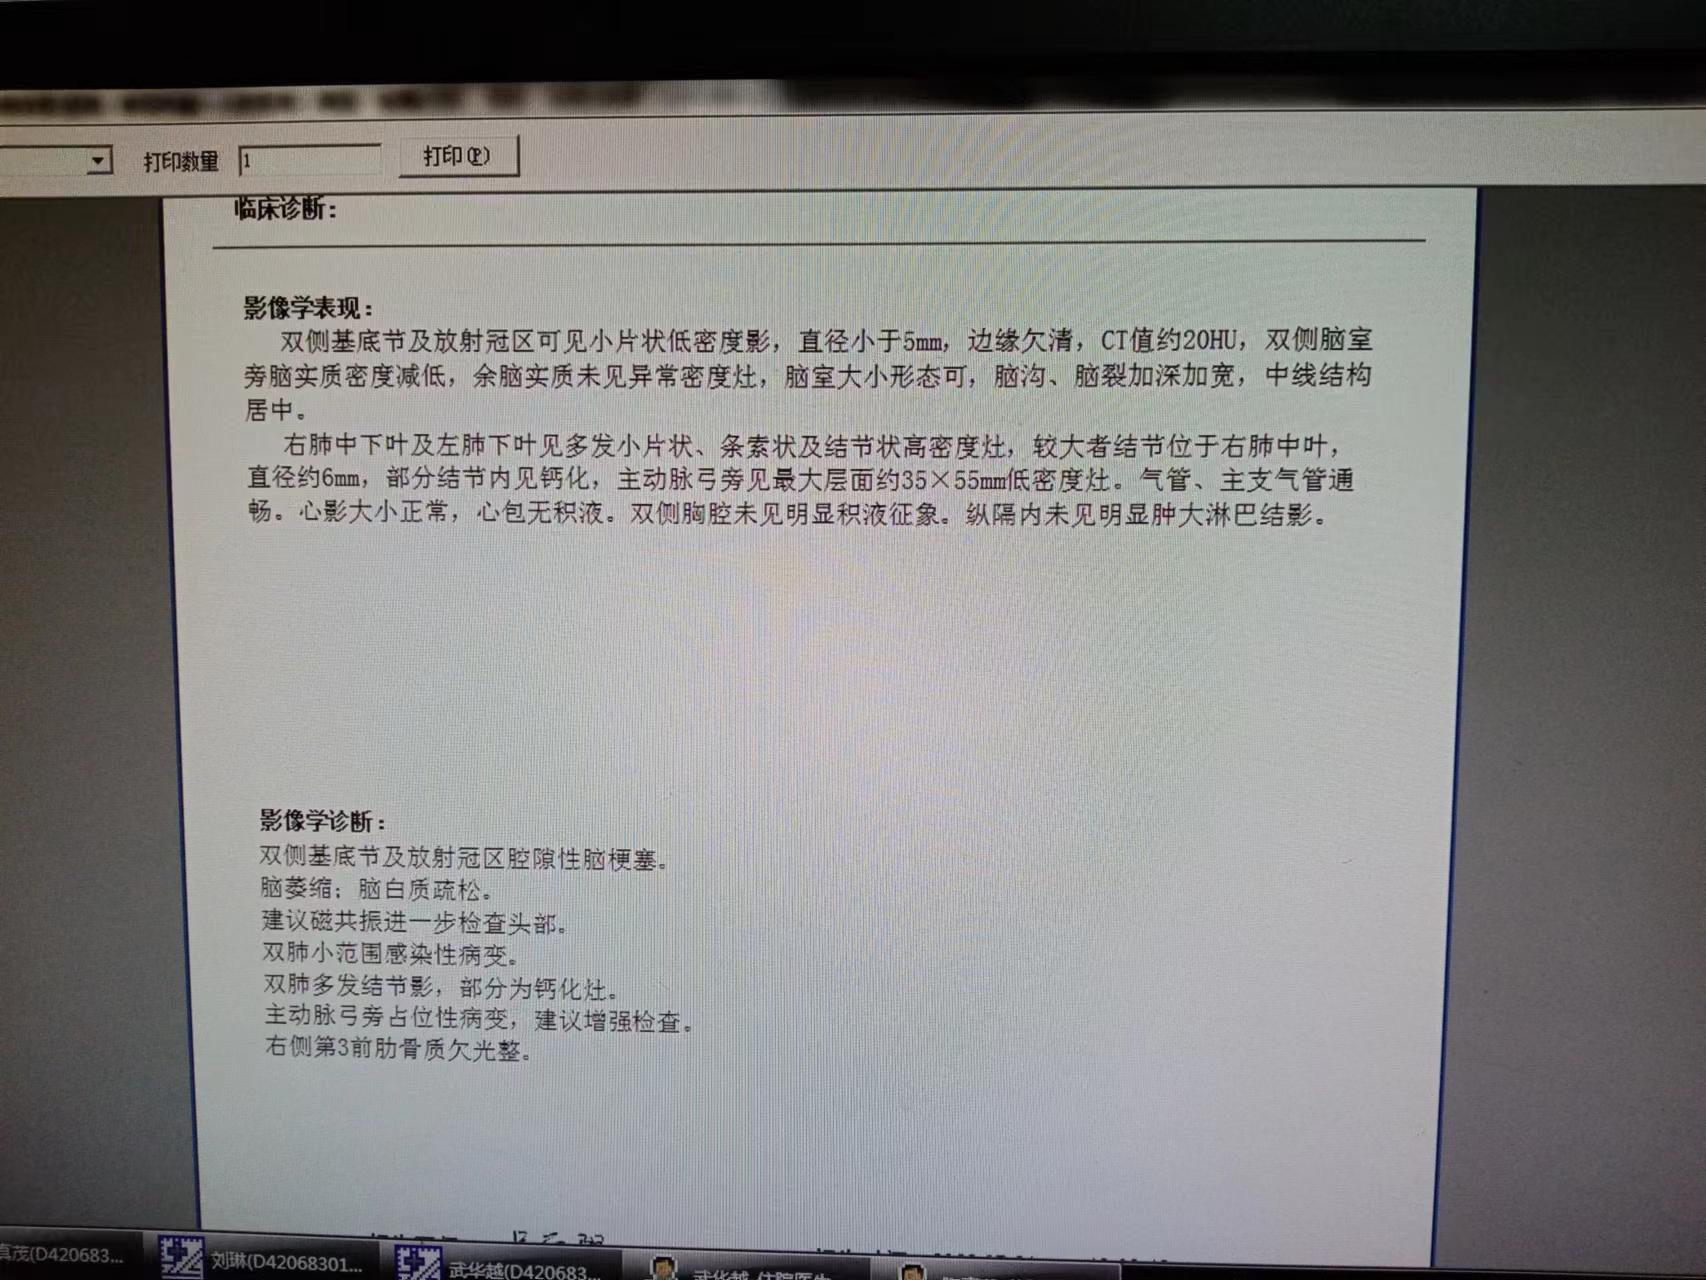

O=O 02023-08-02 患者家属这是我83岁奶奶的报告,哪位朋友能帮忙看看这是到什么阶段了,发展到晚期还有多长时间。 医生说肿瘤挨着血管,做不了手术,年...